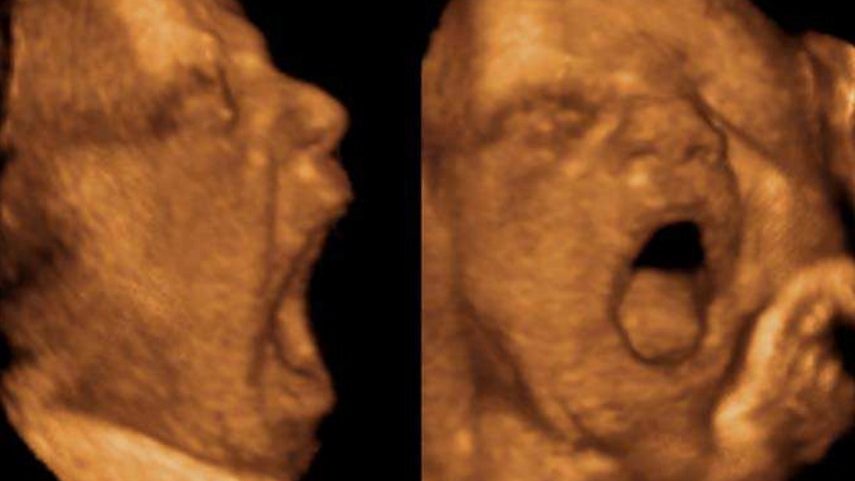

I ricercatori hanno analizzato 32 feti sani attraverso ecografie 4D, esaminando i video frame per frame con un metodo validato che consente di distinguere i veri sbadigli dalle semplici aperture della bocca. Un aspetto metodologico decisivo, perché la confusione tra questi comportamenti ha generato in passato stime non accurate.

La frequenza media osservata è stata di circa 3,6 sbadigli all’ora (mediana circa 2) e non mostra variazioni significative con l’età gestazionale. L’elemento rilevante è invece l’associazione con il peso alla nascita: all’aumentare della frequenza degli sbadigli, il peso risulta lievemente più basso, senza però indicare alcuna condizione patologica.

«Abbiamo riscontrato una relazione negativa tra frequenza degli sbadigli fetali e peso alla nascita», spiega Damiano Menin, docente di Psicologia dello sviluppo all’Università di Ferrara. «Questo dato potrebbe riflettere una risposta legata allo stress anche in feti sani, suggerendo che lo sbadiglio sia coinvolto nei meccanismi di regolazione fisiologica già prima della nascita».

«Distinguere con precisione tra sbadigli e altre aperture della bocca era fondamentale», evidenzia Marco Dondi, professore dell’Università di Ferrara. «Solo con una codifica rigorosa è possibile capire cosa ci dicono davvero questi comportamenti sullo sviluppo prenatale».